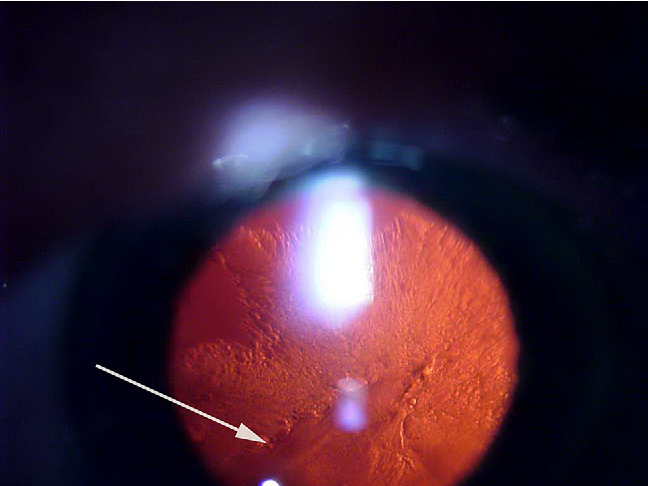

전방에 염증세포들과, 방수흐림(AC flare)이 관찰되고,

전방에 흰물질 덩어리가 관찰됩니다.